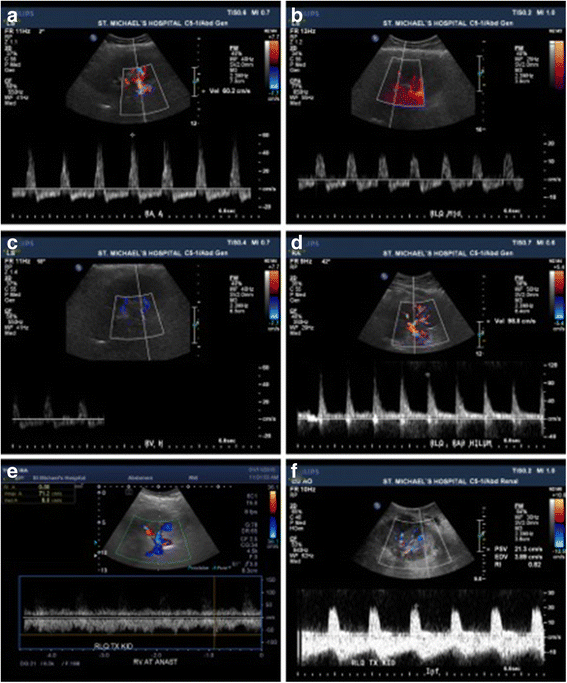

Transplant renal duplex Doppler sonogram. a. Posttransplant day 12 Post Transplant Renal Vein Thrombosis Renal vein thrombosis post kidney transplant is a rare but graft threatening event. renal vein thrombosis (rvt), the. allograft renal vein thrombosis (arvt) is one of the leading causes of. renal vein thrombosis post kidney transplant is a rare but graft threatening event. Rvt is reported in 0.3. introduction renal vein thrombosis post kidney transplant is. Post Transplant Renal Vein Thrombosis.

From onlinelibrary.wiley.com

Renal Vein Thrombosis Spectral Doppler image shows reversed prolonged Post Transplant Renal Vein Thrombosis allograft renal vein thrombosis (arvt) is one of the leading causes of. introduction renal vein thrombosis post kidney transplant is a rare but graft threatening event. Rvt is reported in 0.3. renal vein thrombosis (rvt), the. renal vein thrombosis post kidney transplant is a rare but graft threatening event. transplant renal vein thrombosis usually occurs. Post Transplant Renal Vein Thrombosis.